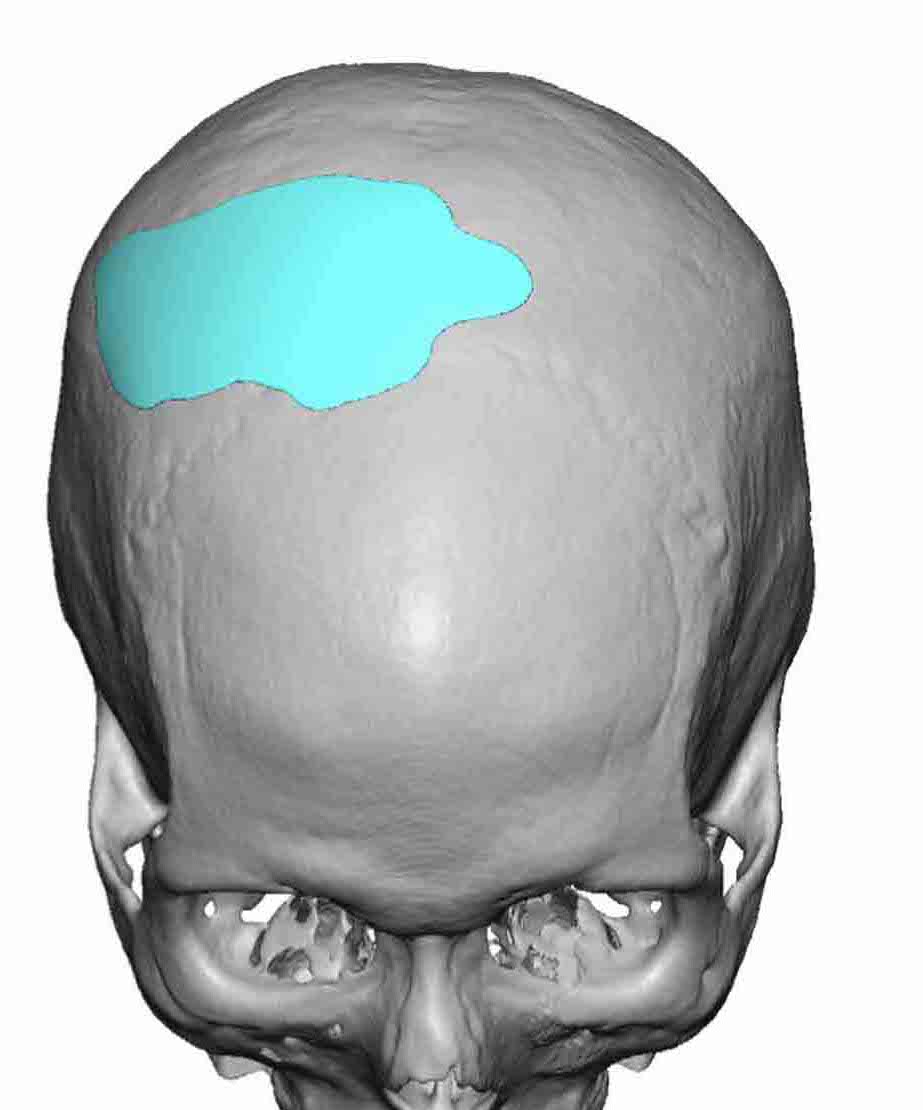

Patient 28

Desire for rounder shape to the top of the head from a congenital parasagittal deficiency skull shape.

Custom skull implant designed to fill in the parasagittal deficiencies.

Desire for rounder shape to the top of the head from a congenital parasagittal deficiency skull shape.

Custom skull implant designed to fill in the parasagittal deficiencies.